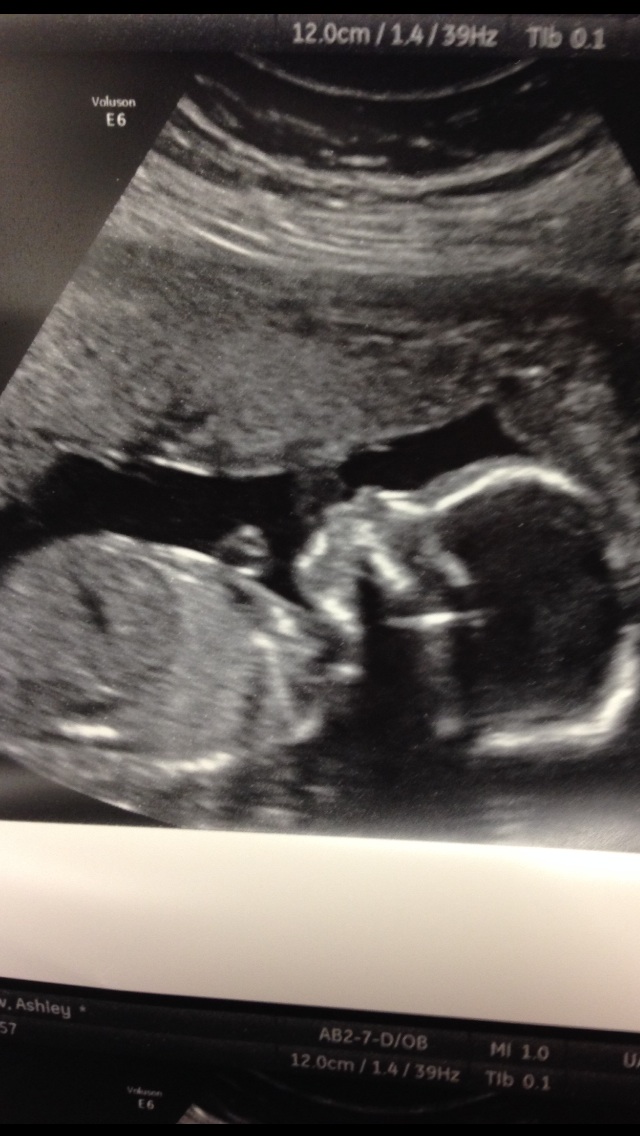

Loving all the updates! I had my AS today. Measuring at 20w2d so almost dead on. Baby weighs 13ish ounces. I can't wait to start feeling baby girl move!

My a/s went wonderfully! Baby is measuring right on track and everything looks great! The tech did mention how big the feet are, which isn't a surprise since my husband and I have huge feet. We found out we are having a beautiful, friendly, rolling, baby girl!

Just got back from mine. Everything is looking great and she is measuring right on track. It was so amazing to see all the details of her hands, feet and face... we even saw her yawn!

I had my A/S this morning. I was so nervous. Doc said everything looks normal. The tech had quite a challenge as L/O was moving around so much. Flipping and wiggling. Saw her wave her fingers. Now it feels so real!

Hey girls. I had my A/S yesterday and everything was perfect. We are definitely having a BOY! He is nice and healthy and we even have a picture showing him smiling. We are beyond thrilled and so happy to have 2 beautiful healthy children!